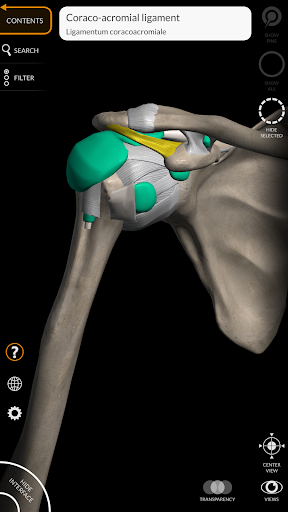

"Anatomy 3D Atlas" memungkinkan Anda mempelajari anatomi manusia dengan cara yang mudah dan interaktif.

Melalui antarmuka yang sederhana dan intuitif, Anda dapat mengamati setiap struktur anatomi dari sudut mana pun.

Model 3D anatomi sangat terperinci dan memiliki tekstur hingga resolusi 4k.

saraf • Sistem pernapasan • Sistem pencernaan • Sistem urogenital (pria dan wanita) • Sistem endokrin • Sistem limfatik • Sistem mata dan telinga FITUR • Antarmuka yang sederhana dan intuitif • Putar dan perbesar setiap model dalam ruang 3D • Opsi untuk menyembunyikan atau mengisolasi satu atau beberapa model yang dipilih • Filter untuk menyembunyikan atau menampilkan setiap sistem • Fungsi pencarian untuk menemukan setiap bagian anatomi dengan mudah • Fungsi penanda untuk menyimpan tampilan khusus • Rotasi cerdas yang menggerakkan pusat rotasi secara otomatis • Fungsi transparansi • Visualisasi otot melalui tingkat lapisan dari yang superfisial hingga yang terdalam • Dengan memilih model atau pin, istilah anatomi terkait akan muncul • Deskripsi otot: asal, • Tampilkan/ Sembunyikan antarmuka UI (sangat berguna dengan layar kecil) MULTIBAHASA • Istilah anatomi dan antarmuka pengguna tersedia dalam 11 bahasa: Latin, Inggris, Prancis, Jerman, Italia, Portugis, Turki, Rusia, Spanyol, Mandarin, Jepang, dan Korea • Istilah anatomi dapat ditampilkan dalam dua bahasa secara bersamaan PERSYARATAN SISTEM • Android 8.0 atau yang lebih baru, perangkat dengan RAM minimal 3GB Reversi

Ligamen ditambahkan